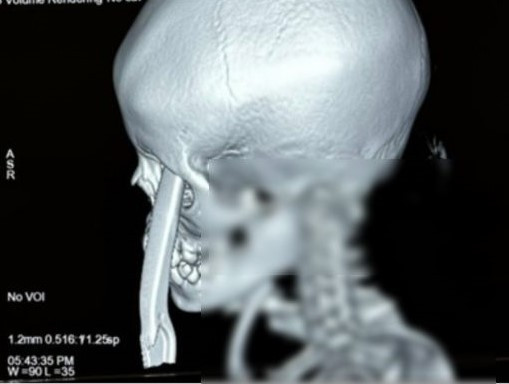

Kết quả chụp CT sọ não cho thấy có xuất huyết cấp trong nhu mô não, xuất huyết ngoài và dưới màng cứng vùng trán, vỡ phần mặt ổ mắt của xương trán, tụ máu trong xoang hàm. Dị vật từ bên ngoài vào hốc mắt và xuyên hốc mắt trái, xuyên sàn sọ vào nhu mô não.

Tại phòng mổ, các bác sĩ Ngoại thần kinh phẫu thuật mở sọ, lấy nhu mô não dập, máu tụ, mảnh xương vỡ. Bác sĩ Bệnh viện Mắt phối hợp lấy dị vật có chiều dài 25cm ra khỏi hốc mắt của trẻ.